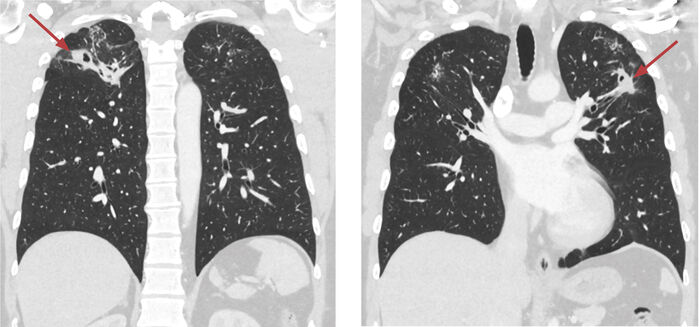

Mynd 2. Tölvusneiðmynd af lungum hjá sjúklingi sem sýnir íferðarfláka ofan til í báðum lungum með holumyndun (cavitation) (rauð ör).

TS af lungum sýndi umtalsverðar breytingar í efri lungnablöðum, en þar sáust nokkrir íferðarflákar í báðum lungum ásamt byrjandi holumyndun (Mynd 2). TS af kviðarholi var án athugasemda. Berklar voru taldir vera líklegasta greiningin út frá þessum rannsóknum þrátt fyrir lítil einkenni. Í framhaldinu var ráðlagt að fá þrjú hrákasýni og senda í litun fyrir sýruföstum stöfum og í berklaræktun. Einnig var sent blóðsýni í HIV-rannsókn og IGRA-próf (interferon gamma release assay) (Quantiferon®).